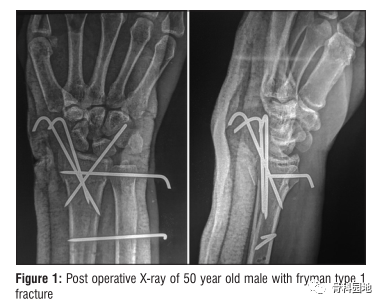

首先进行闭合复位,在透视机监护下以确认复位满意,然后按以下顺序进行骨折固定:

1.自桡骨茎突斜向内侧、

2.桡骨内侧角背侧至掌外侧

3.自Lister结节背侧至掌侧方向

4.骨折远端和近端尺桡骨横行固定。